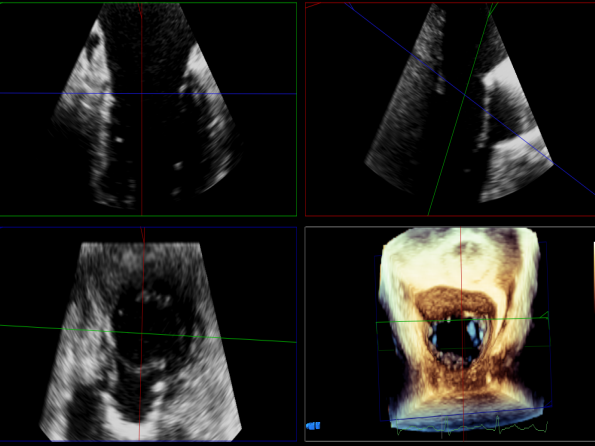

术中超声

P2区脱垂,宽14.8mm,Gap:3.3mm

3D-color,返流重度,3+级

麻醉状态下左肺静脉血流频谱

MVA:6.67cm²

房间隔穿刺点选择

穿刺高度:4.3cm

三维评估两个夹子位置

3D-color再次确定未见残余分流

评估瓣口条件,平均跨瓣压差:4mmHg

肺静脉血流频谱恢复正常